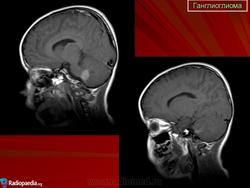

Ганглиоглиома